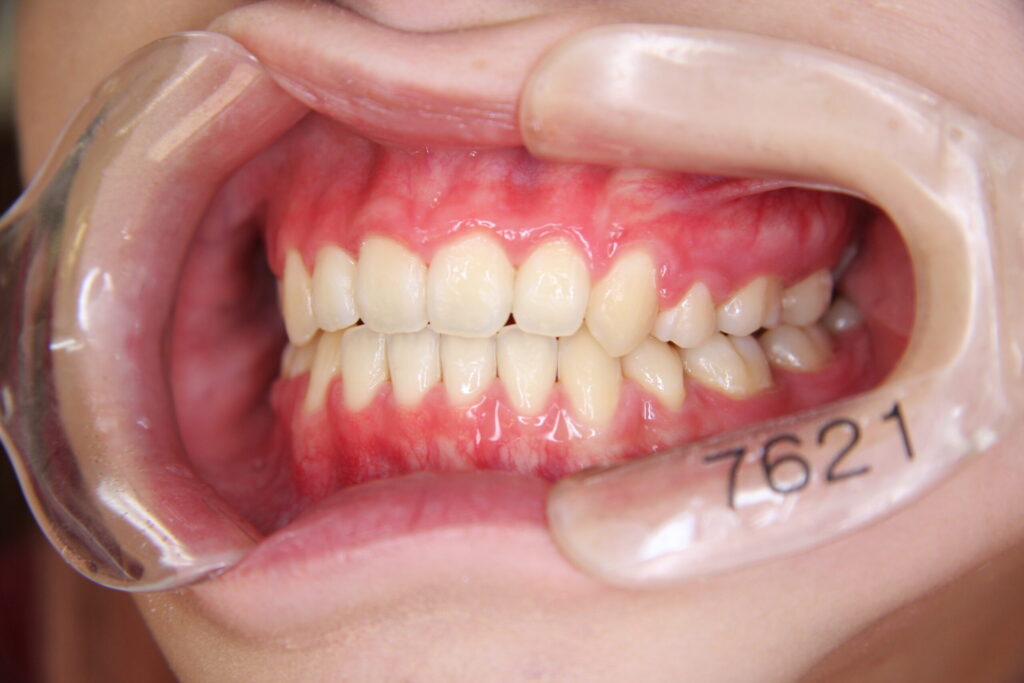

「カマクラデントフェイシャルオーソピディクスオリジナルの取り外しの効くミニマムアクチベータの治療結果」

「子どもの矯正歯科」 「日本歯科専門医機構認定矯正歯科専門医  山本一宏の blog 」 日本歯科専…